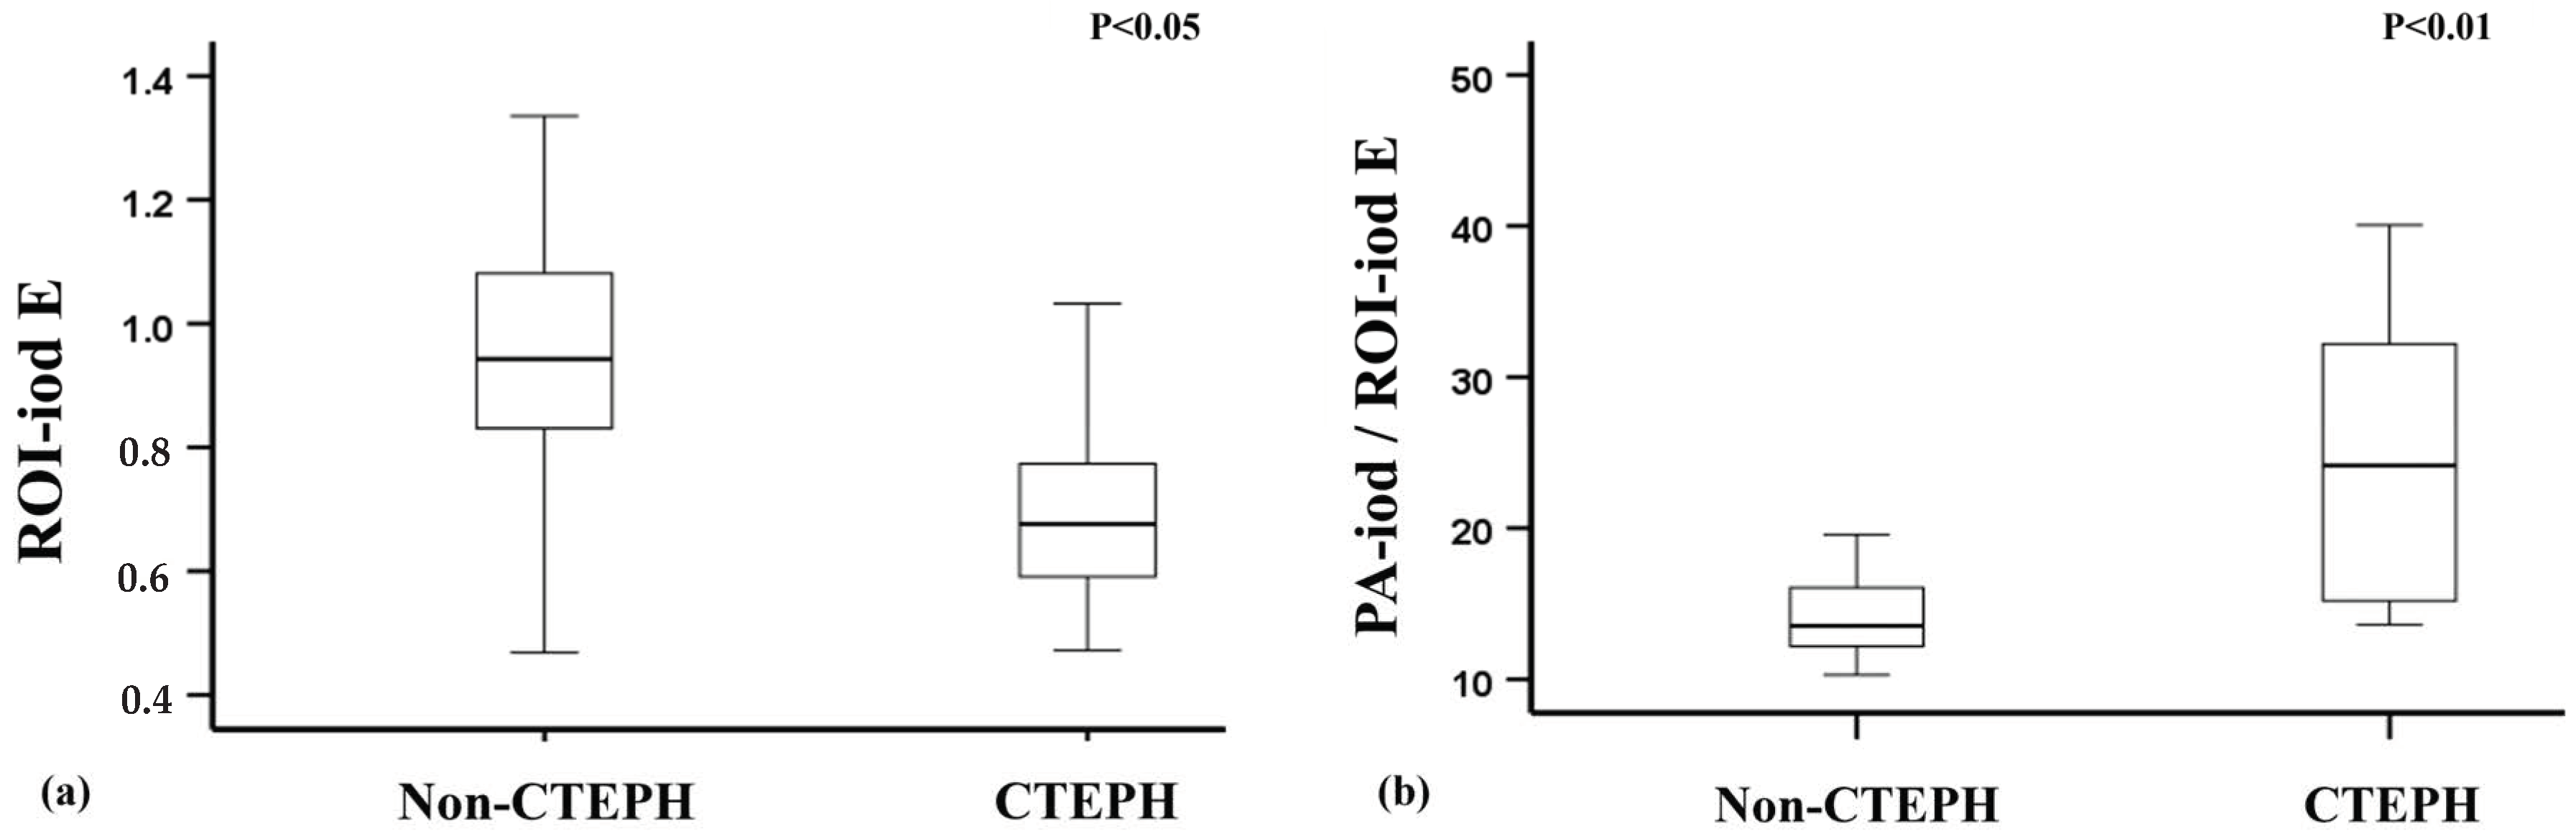

3.3. Differentiation Between CTEPH Patients and Non-CTEPH Patients

- Among PH subtypes, patients with chronic thromboembolic pulmonary hypertension (CTEPH) exhibit even higher PA-iod/ROI-iod ratios than those with other forms of PH.

| Non-CTEPH (n = 24) | CTEPH (n = 9) | p-Value | |

| ROI-iod A | 1.04 (0.83–1.26) | 0.76 (0.67–0.87) | 0.006 ** |

| ROI-iod B | 0.96 (0.73–1.10) | 0.72 (0.63–0.92) | 0.043 * |

| ROI-iod C | 0.84 (0.74–1.07) | 0.63 (0.49–0.85) | 0.035 * |

| ROI-iod D | 0.95 (0.75–1.13) | 0.65 (0.46–0.86) | 0.026 * |

| ROI-iod E | 0.94 (0.82–1.09) | 0.68 (0.58–0.87) | 0.015 * |

| PA-iod/ROI-iod A | 13.16 (10.90–14.64) | 20.32 (14.0131.74) | 0.005 ** |

| PA-iod/ROI-iod B | 13.83 (12.33–16.74) | 21.33 (15.88–29.70) | 0.005 ** |

| PA-iod/ROI-iod C | 13.43 (12.26–17.59) | 24.25 (15.23–42.08) | 0.012 * |

| PA-iod/ROI-iod D | 13.81 (12.05–17.66) | 27.52 (15.13–40.81) | 0.010 * |

| PA-iod/ROI-iod E | 13.54 (12.17–16.21) | 24.16 (14.56–33.63) | 0.006 ** |